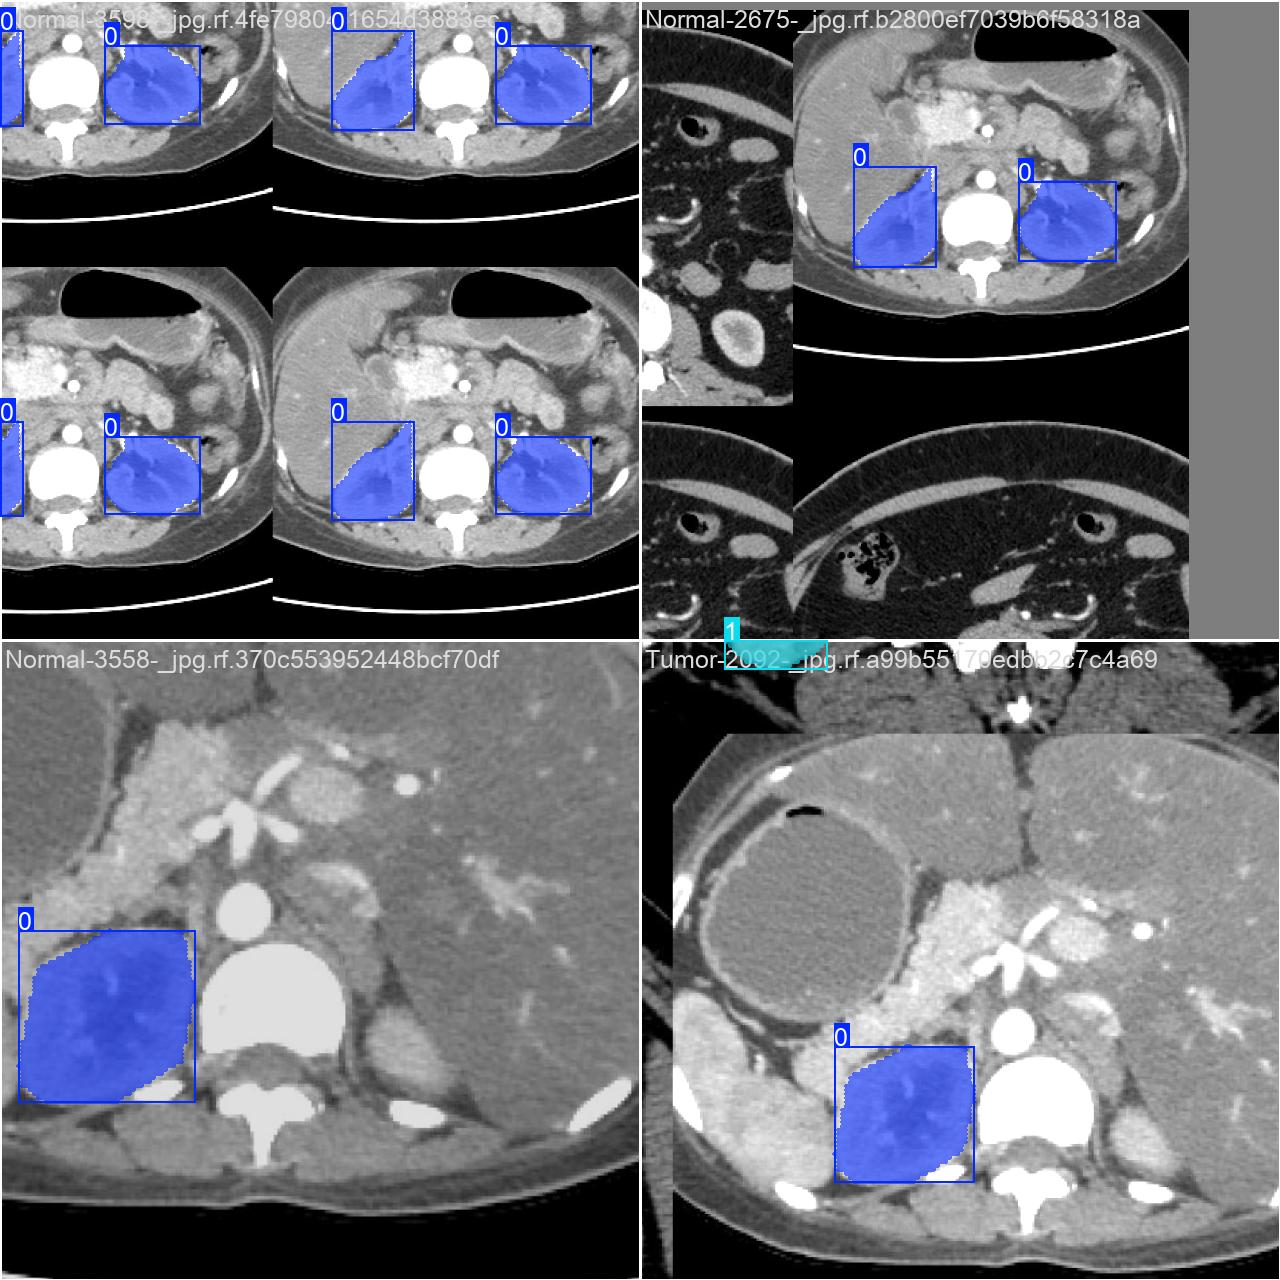

部分数据集图像如下图所示:

部分标注如下图所示: